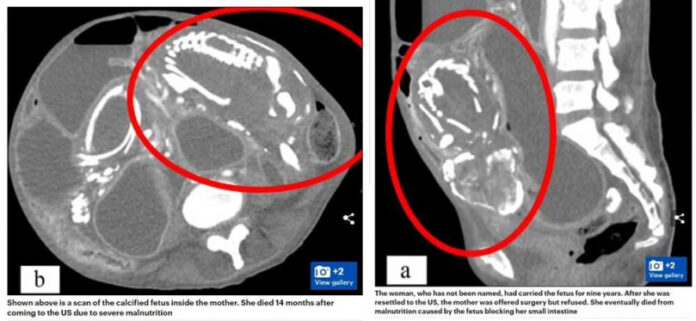

自此之后,她便对于医疗人员有非常大的排斥。9年后妇女因为慢性腹绞痛、消化不良等原因,到医院进行检查,这时医生才发现,9年前死掉的胎儿因为没有引产,此时竟在妇女的腹中形成罕见的「石胎」(Lithopedion),就连孩子的骨架都能明显看见。

不过因为妇女过去的经验,她认为自己的胎儿会形成石胎,都是因为遭到诅咒,因此她拒绝动手术将石胎取出。14个月后,因为胎儿阻挡了妇女的肠道吸收重要营养素,她最终因为营养不良死亡。